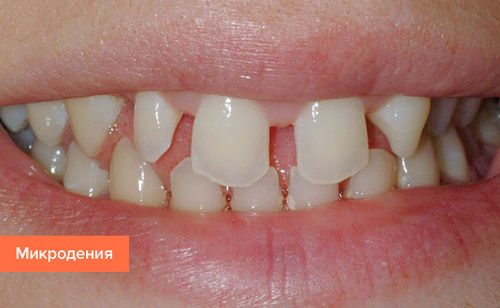

Проблема у пациентов диагностируется достаточно редко. Выделяют несколько форм патологий величины зубов. Микродентия характеризуется наличием мелких по сравнению с нормой элементов в ротовой полости. Проблема наблюдается в двустороннем порядке, реже проявляется с одной стороны челюсти. При микродентии элементы отличаются неправильной формой.

В стоматологии микродению подразделяют еще на несколько форм: изолированную, относительную и генерализованную. В первом случае обнаруживается 1-2 зуба, которые имеют аномальные размеры. Чаще всего видоизменяются боковые резцы. При относительном типе проблемы зубы имеют нормальные размеры, но из-за больших пропорций челюсти визуально кажутся маленькими. Генерализованная микродентия – наличие мелких единиц по всей длине челюсти.

Микродентия – мелкие зубы, размеры их меньше среднестатистических параметров. Диагностируется визуально, чаще всего у боковых и верхних резцов. Зубы растут с большими промежутками и являют собой достаточно серьезную проблему эстетического характера.

Малый размер (микродентия) предполагает слишком большие межзубные промежутки. Такая патология ухудшает внешний вид. Лечение проводится путем установки новых коронок.

Микродентия относится к заболеваниям, характеризующимся прорезыванием постоянных зубов с аномальным развитием их размеров.

При данной патологии, они имеют меньшие размеры не только в диаметре, но и высоте, хотя высота, чаще, всего лишь незначительно отличается от среднестатистической нормы.

В основном, патология охватывает зубы переднего или бокового отдела, но может поражать и весь зубной ряд. Особенно подвержены заболеванию боковые и центральные резцы.